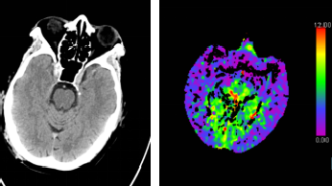

腦CT沒(méi)事就代表大腦沒(méi)事嗎?深入探討腦部健康與CT檢查的關(guān)系,腦部健康與CT檢查,CT無(wú)異常是否代表大腦無(wú)隱患?

摘要:腦部健康與CT檢查的關(guān)系并非簡(jiǎn)單等同。雖然腦CT檢查可以檢測(cè)腦部結(jié)構(gòu)異常和損傷,但并不能完全排除所有潛在疾病。腦部健康涉及更多方面,如功能狀態(tài)、神經(jīng)傳導(dǎo)等,CT檢查無(wú)法全面評(píng)估。腦CT沒(méi)事不代表大腦一定沒(méi)問(wèn)題,...